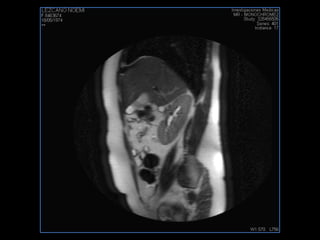

PROTOCOLO pelvis SAG T2, Y FAT SAT (FINOS) AXIAL T1  AX FAT SAT CON   GADOLINIO :  AX T1 Y COR T1 SAT: NO  FASE: RL THK: 3MM  COIL:  GAP: (FACTOR 1.4) 1MM FOV: 40 CM NEX:2 SINCRONIZACION RESPIRATORIA EN 3 O 4 CICLOS ALE